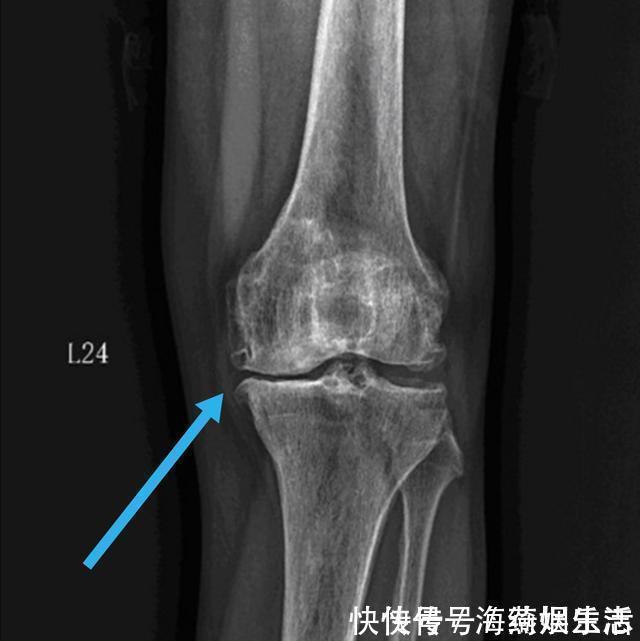

我们的膝关节实际上有三块骨头组成,分别是大腿骨,小腿骨,还有膝盖正面的、圆形的髌骨。髌骨是我们每个人都能摸到的,你用手放在你的膝盖正前方就能触摸到一个圆形的,像盖子一样的圆骨头,只要你的大腿肌肉是放松状态,那么髌骨就是可以左右推动的。那么既然是三块骨头,它们就构成了两个不同的接触面。一个呢,很好理解,是大腿和小腿骨之间的接触面,这个关节面是让我们负重用的。不论我们是站着、走路、跳跃,只要有体重压在膝盖上,这个关节面就承担压力。而我们人体膝关节的结构,决定了内侧关节受力多,约占整个重量的60?外侧关节面受力少,约占40?所以往往都是膝盖内侧磨损的快,内侧关节间隙,首先出现狭窄,所以很多人膝关节炎,刚开始的症状会有膝盖内侧的疼痛,久而久之,也会出现O型腿,也叫膝内翻,这就是因为膝盖内侧的软骨等结构已经被磨损殆尽。

如图所示,内侧关节缝隙比外侧变得狭窄了,膝盖的外观也就变成罗圈腿了。当出现这些症状的时候,我们就会开始出现走路疼痛。一般都是先有内侧疼,然后逐渐发展到整个关节都疼。等到走平地都不能走了,每一步都疼的时候,往往这个时候就需要做保膝手术或关节置换等手术治疗了。除此之外呢,我们的膝盖还有一个关节面,叫做髌股关节。也就是刚才我们摸的那个圆骨头深部的软骨面。这个部位比较特殊,当我们伸直腿,也就是走路的时候,这个关节面的压力是比较小的,甚至软骨和软骨之间都是不接触的。这是为什么刚才我们在伸直并放松大腿肌肉的时候,髌骨可以推动的原因。